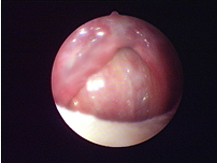

全新SURGITRON DUAL RF 120IEC,擁有更美的外觀,更強(qiáng)的性能,優(yōu)越的射頻止血功能,作為同時(shí)擁有4.0 Mhz和1.7Mhz的雙射頻產(chǎn)品,能應(yīng)用于更多的科室手術(shù)。